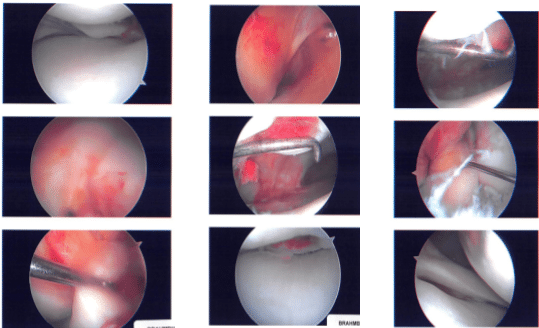

Intraoperative images

We went over the arthroscopic pictures and removed the stitches during the visit. We will continue with ice and elevation of the knee to decrease swelling and pain. We will continue to utilize early mobilization and mechanical prophylaxis to reduce the chances of a deep vein thrombosis.